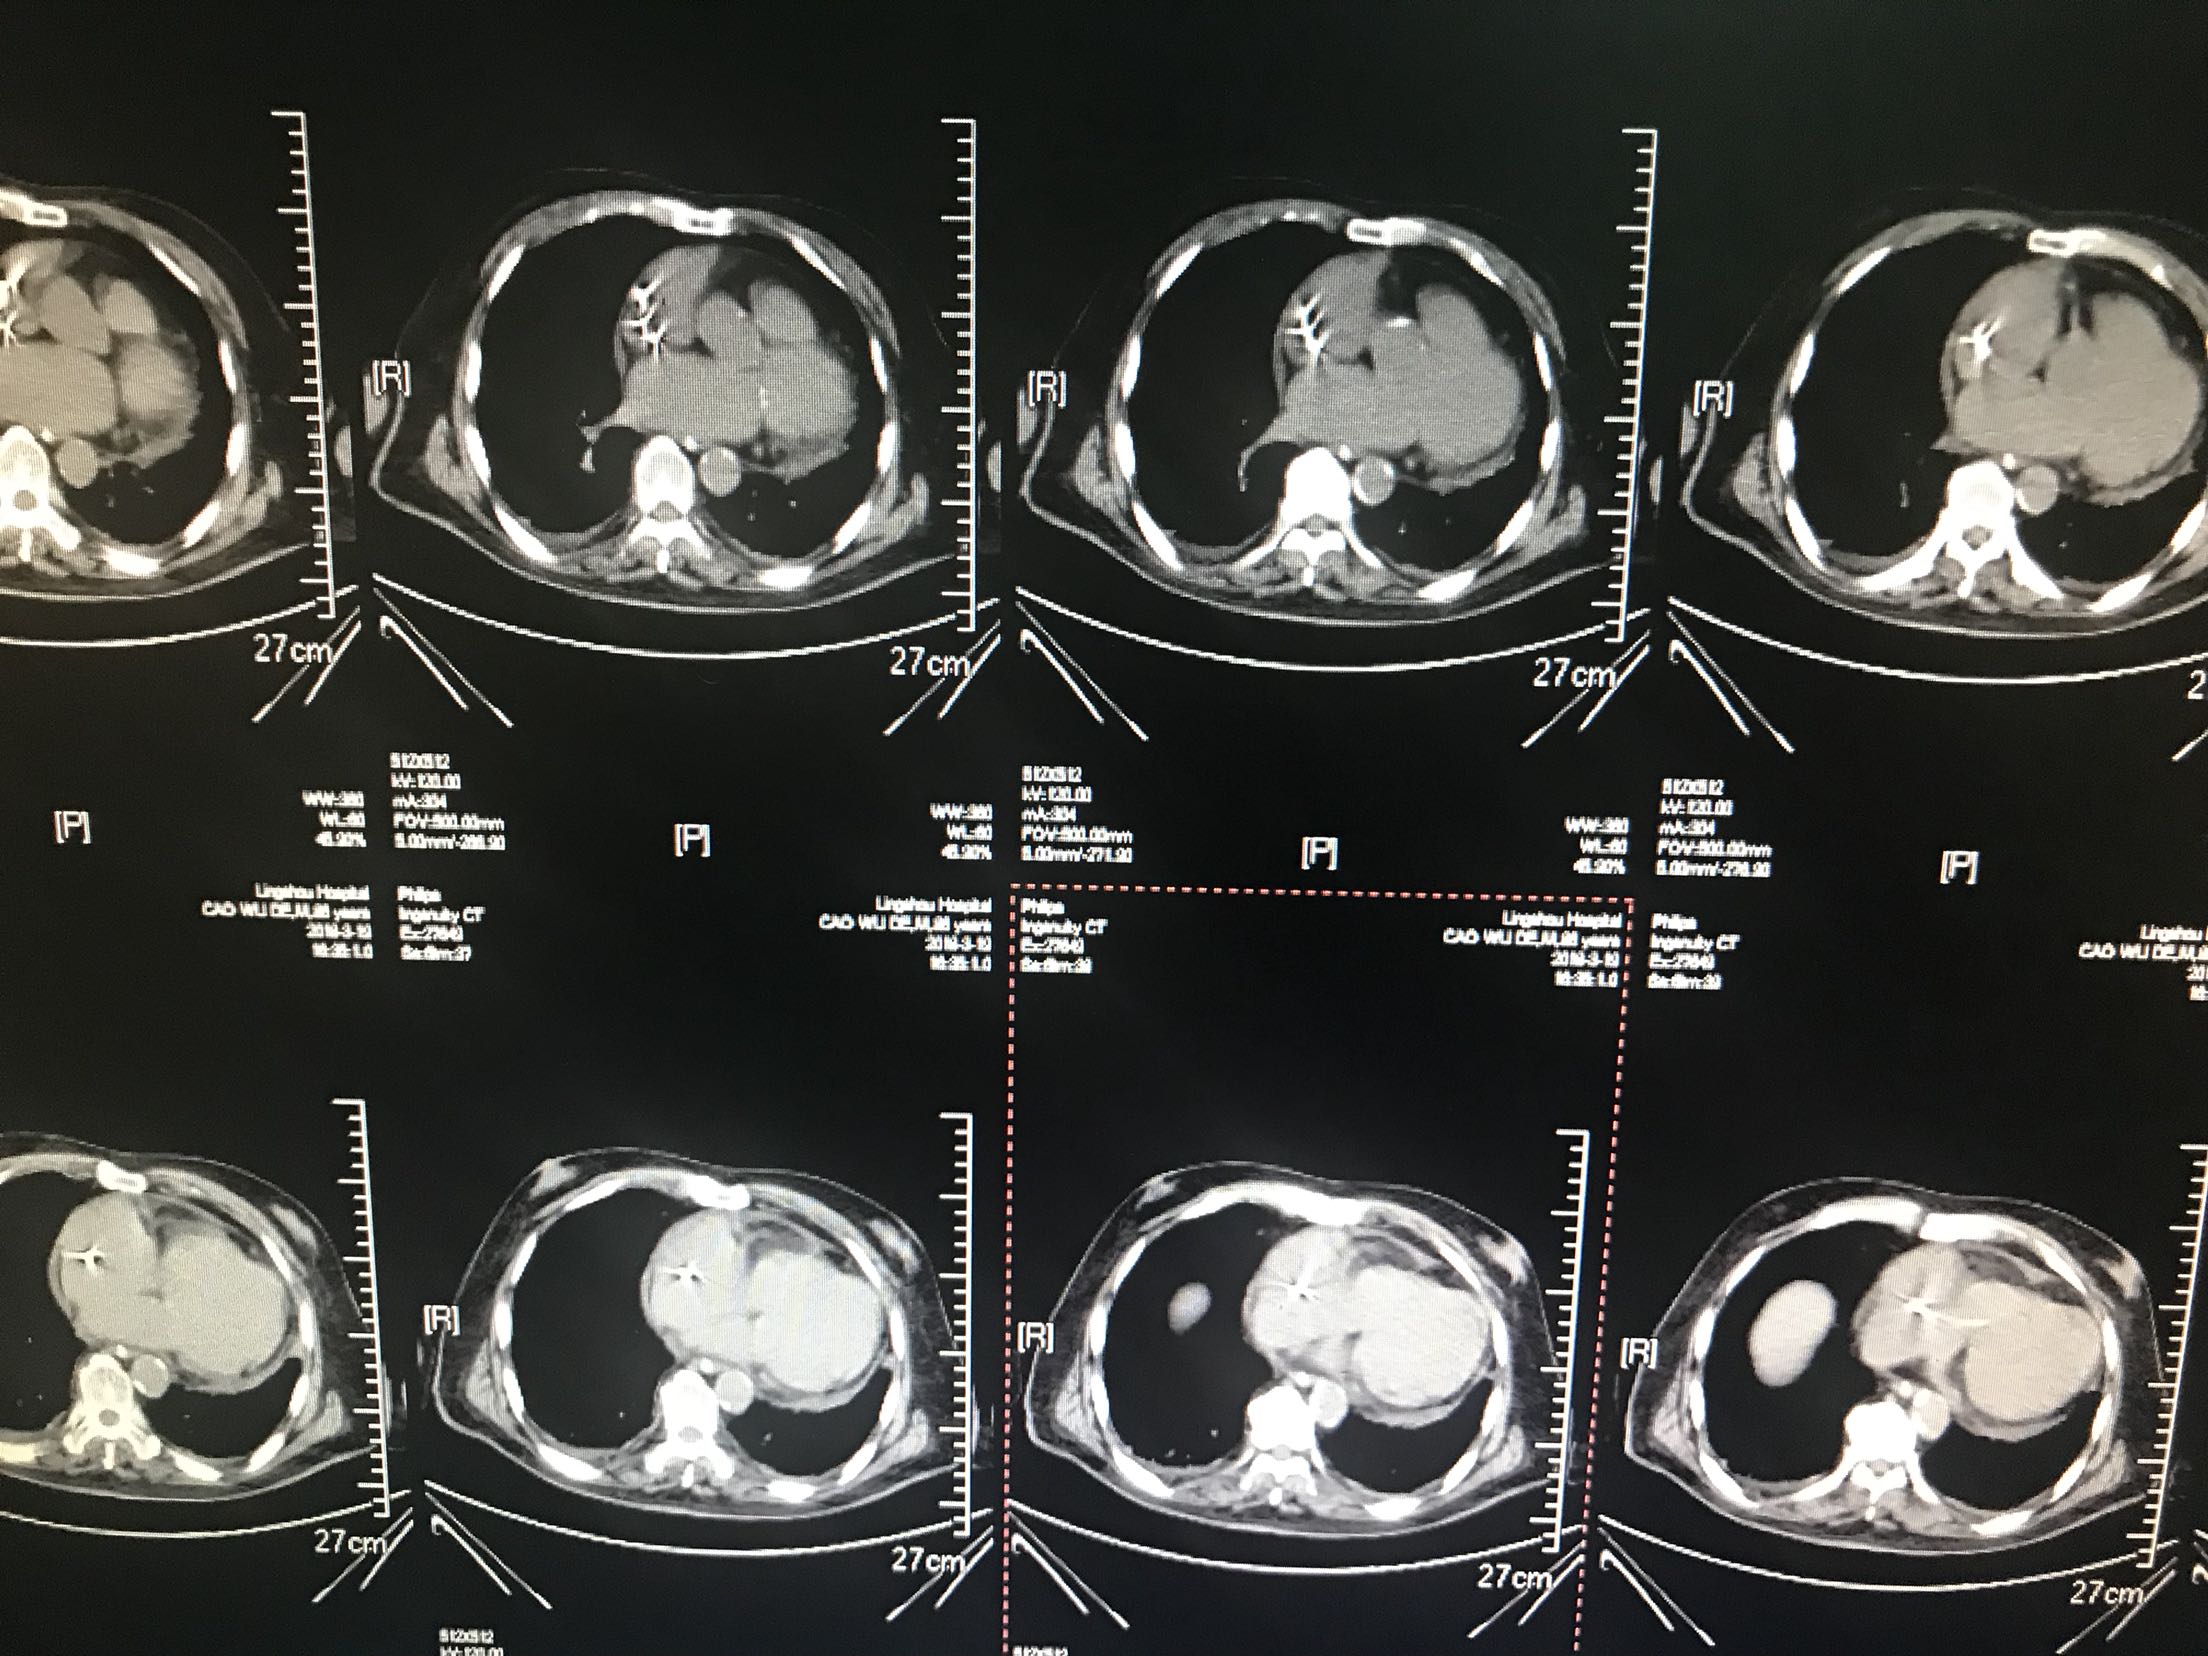

患者88岁不能行走1小时入院,房颤心衰起搏器安装痴呆病史,患者1小时前被家人发现倒在地上,不能言语,不能行走,急诊查血压210/120mmhg,查透头颅Ct够收住院

体温37.5℃脉搏95次/分,呼吸22次/分,血压135/87mmhg,意识模糊,,眼动充分,无明显眼震,颈无抵抗,双肺呼吸音清,未闻及干湿性啰音,心音低钝,心律不规整,未闻及杂音,双下肢可见不自主运动,霜巴氏征阳性,克氏征阴性,